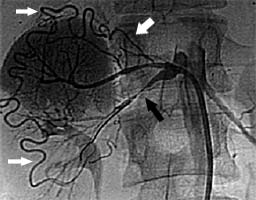

Фибромускулярная дисплазия у пациента 14 лет. Субтотальный стеноз нижнеполюсной почечной артерии (черная стрелка). Кровоснабжение нижнего полюса почки за счет расширенной капсулярной артерии (белые стрелки) |